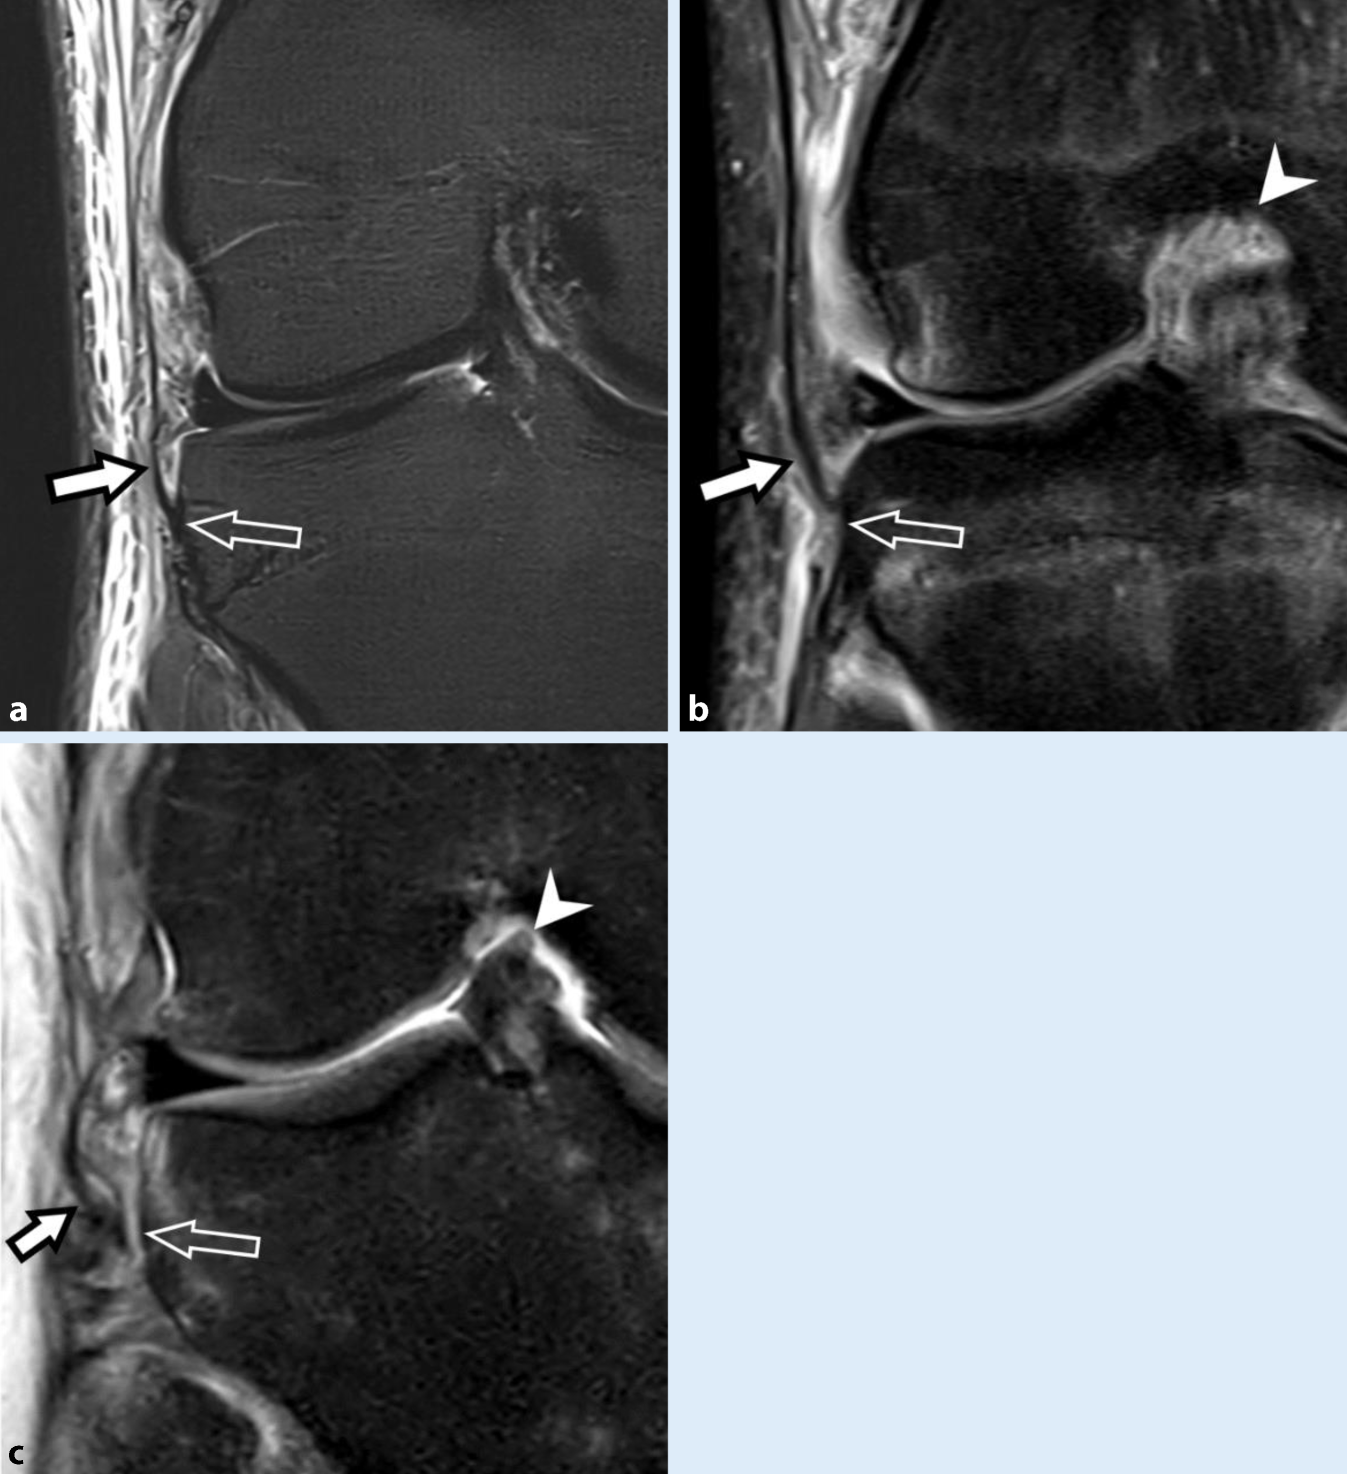

Abb. 6

MRT des Kniegelenks von drei unterschiedlichen Patient:innen nach jeweils akuter Kniedistorsion. Koronale Short-Tau-Inversion-Recovery(STIR)-Sequenzen mit Schnittführung und Vergrößerung des anterolateralen Kompartiments mit Darstellung des anterolateralen Ligaments. a Intaktes anterolaterales Ligament (ALL) mit flacher, hypointenser Konfiguration (weißer Pfeil) und normaler distaler Insertion (hohler Pfeil), welches sich durch die umgebenden Weichteilödeme gut demaskiert. b Partialruptur des ALL mit partieller Faserunterbrechung an der tibialen Insertion (hohler Pfeil) und Verdickung des distalen Ligamentanteils (weißer Pfeil). c Vollständige Ruptur des ALL mit Ablösung von der tibialen Insertion (hohler Pfeil), geringer Retraktion und welliger Konfiguration (weißer Pfeil) sowie umgebenden Ödemen. In Bild b und c ist jeweils eine Ruptur des vorderen Kreuzbands partiell mitabgebildet (Pfeilspitzen), mit welcher eine Verletzung des ALL typischerweise assoziiert ist